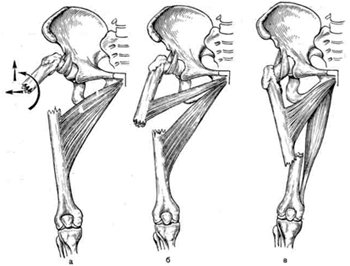

Классификация переломов диафиза бедренной кости: Иллюстрации и информация